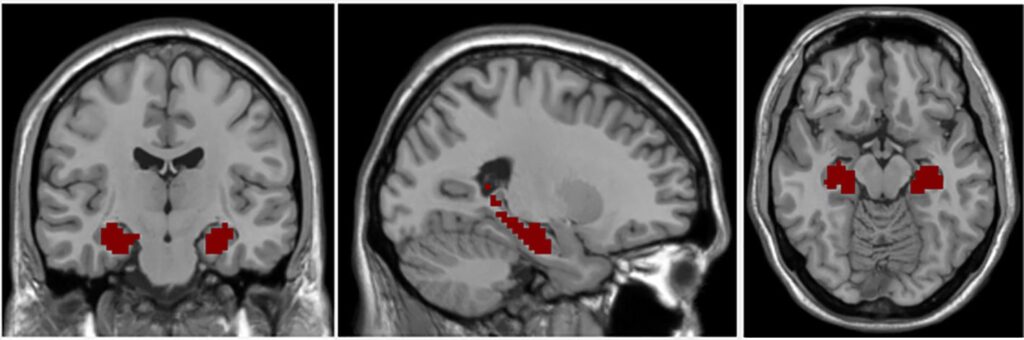

Ved hjælp af avancerede scanningsteknikker som MR-scanning (magnetisk resonans) har forskere observeret, at hippocampus ofte er mindre i volumen hos personer med skizofreni sammenlignet med raske kontrolpersoner. Men det er ikke kun størrelsen, der er anderledes. De mest signifikante fund peger på problemer med hjernens 'ledningsføring' – altså de synaptiske forbindelser mellem nervecellerne.

Forskere har observeret, at forandringerne ofte er mere udtalte i den venstre hjernehalvdel. Den præcise årsag er ukendt, men det kan hænge sammen med hjernens lateralisering, hvor forskellige funktioner er dominerende i hver sin side. Venstre hjernehalvdel er for eksempel stærkt involveret i sprog, en funktion der ofte er forstyrret ved skizofreni. Den asymmetriske påvirkning er endnu et bevis på, hvor specifik og kompleks sygdommens patologi er.